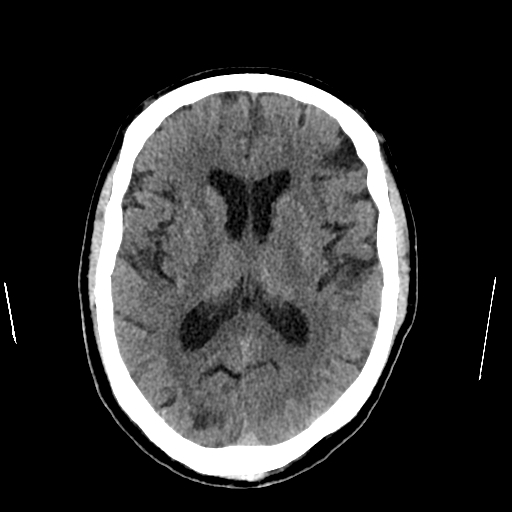

Se realiza tomografía cerebral simple de urgencia, identificándose múltiples áreas de hipodensidad cortico-subcortical distribuidas en ambos hemisferios cerebrales, compatibles con eventos vasculares isquémicos en distintos estadios evolutivos.

En el hemisferio derecho se observa:

- Hipodensidad occipital compatible con evento isquémico agudo/subagudo

- Área parietal sugestiva de evento subagudo/crónico

- Zona de encefalomalacia temporal posteroinferior compatible con infarto crónico

En el hemisferio izquierdo se identifican:

- Hipodensidad cortico-subcortical frontal sugestiva de evento subagudo/crónico

- Lesión parietal compatible con evento subagudo/crónico

- Hipodensidad globular subcortical occipital sugestiva de evento subagudo

No se evidencian colecciones hemorrágicas ni efecto de masa significativo al momento del estudio.

Los hallazgos son compatibles con cerebro multiinfarto, con lesiones bilaterales en diferentes territorios vasculares, patrón que sugiere posible etiología cardioembólica, especialmente por la distribución multifocal y bilateral.